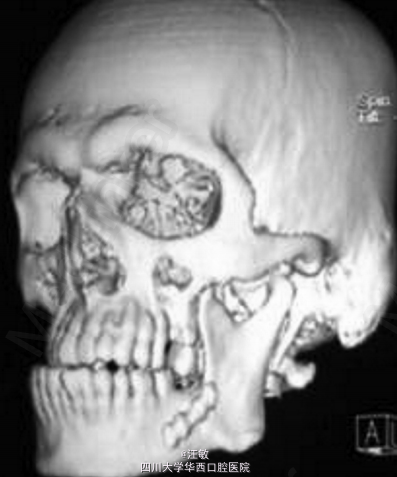

综合临床和影像诊断为左侧髁突骨软骨瘤

病例中患者有明显的面部不对称,但是全景片并未发现有明显异常。此时计算机断层扫描可以帮助临床医生更加准确的确定病损区域。有趣的是病例中CT扫描可以明显发现左侧髁突增大,但是三维重建却发现左髁突外观正常。 doi:org/10.1016/j.jobcr.2014.12.001